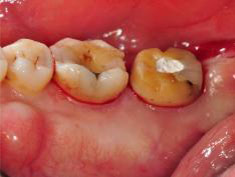

牙周初診時患者之口內觀。口內明顯牙菌斑及牙結石堆積。全口嚴重牙齦紅腫。治療前X光片。#37的近心側有較深的骨內缺損,剩餘齒槽骨高度只有20%。

第一階段牙周基本治療後,牙齦發炎狀況明顯獲得改善。